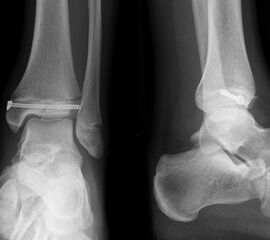

Die häufig nicht dislozierten knöchernen Ausrisse können konservativ behandelt werden. Dislozierte Fragmente sollten operativ mit Kirschner-Drähten oder Schrauben fixiert werden (Abb. 32). Die Nachbehandlung umfasst eine 4-wöchige Entlastung im US-Gips. Eine Röntgenkontrolle erfolgt nach Gipsabnahme. Freies Gehen sollte nach 6 Wochen möglich sein. Danach ist auch eine sportliche Belastung des Sprunggelenks möglich (v. Laer 2013).

Eingebrachtes Osteosynthesematerial sollte vor der Vollbelastung entfernt werden.